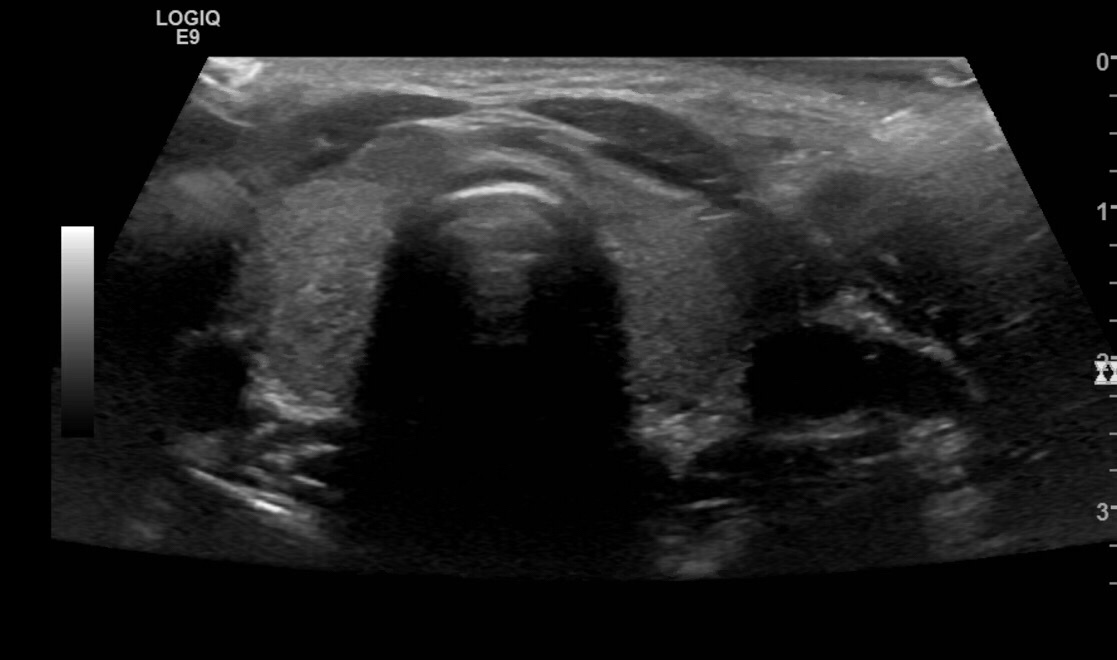

Normal Thyroid Ultrasound Images MyEndoConsult Thyroid Ultrasound Area Thyroid ultrasound uses sound waves to produce pictures of the thyroid gland within the neck. It does not use ionizing radiation and is commonly used to evaluate lumps or nodules. The best place to begin the exam is in the midline directly over the trachea, as it is the easiest landmark to identify by physical exam. This article discusses what. Thyroid Ultrasound Area.

Ultrasound of the Normal Thyroid with Technical Pearls and Pitfalls Thyroid Ultrasound Area The best place to begin the exam is in the midline directly over the trachea, as it is the easiest landmark to identify by physical exam. A thyroid ultrasound is used to examine the thyroid for abnormalities, including: It does not use ionizing radiation and is commonly used to evaluate lumps or nodules. Thyroid ultrasound uses sound waves to produce. Thyroid Ultrasound Area.